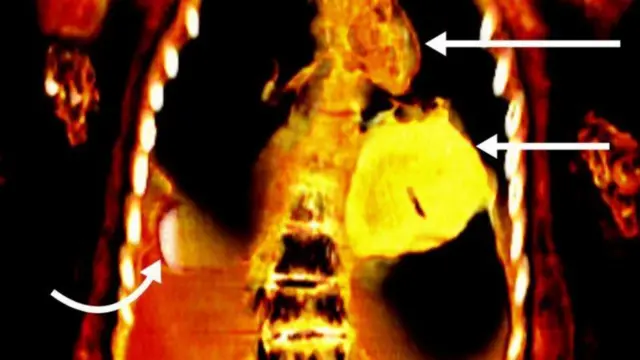

ஒரு நூற்றாண்டுக்கும் மேலாக இந்த உடல் வல்லுநர்களால் முழுமையாக ஆய்வு செய்யப்படாமல் இருந்த நிலையில், கெய்ரோ பல்கலைக்கழகத்தைச் சேர்ந்த சஹர் சலீம் தலைமையிலான குழு சிடி ஸ்கேனரை பயன்படுத்தி மம்மியை ஆய்வு செய்தபோது இந்த உண்மை தெரியவந்துள்ளது.

"கம்ப்யூட்டட் டோமோகிராஃபி கதிரியக்க துறையில் ஏற்பட்ட குறிப்பிடத்தக்க முன்னேற்றத்தைக் காட்டுகிறது. ஒரு படத்தைப் பயன்படுத்துவதற்குப் பதிலாக, இதன் மூலம் உடலின் சிறு பகுதிகளின் நூற்றுக்கணக்கான கணிப்புகளை ஒன்றிணைத்து முழுமையான முப்பரிமாண மாதிரியை உருவாக்க முடியும்" என்றும் சலீம் கூறுகிறார்.